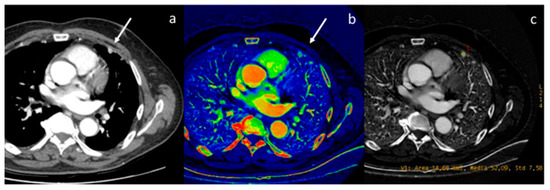

- Lennartz, S.; Le Blanc, M.; Zopfs, D.; Hokamp, N.G.; Abdullayev, N.; Laukamp, K.R.; Haneder, S.; Borggrefe, J.; Maintz, D.; Persigehl, T. Dual-Energy CT-derived Iodine Maps: Use in Assessing Pleural Carcinomatosis. Radiology 2019, 290, 796–804. [Google Scholar] [CrossRef]

- Zhang, X.; Duan, H.; Yu, Y.; Ma, C.; Ren, Z.; Lei, Y.; He, T.; Zhang, M. Differential diagnosis between benign and malignant pleural effusion with dual-energy spectral CT. PLoS ONE 2018, 13, e0193714. [Google Scholar] [CrossRef] [PubMed]